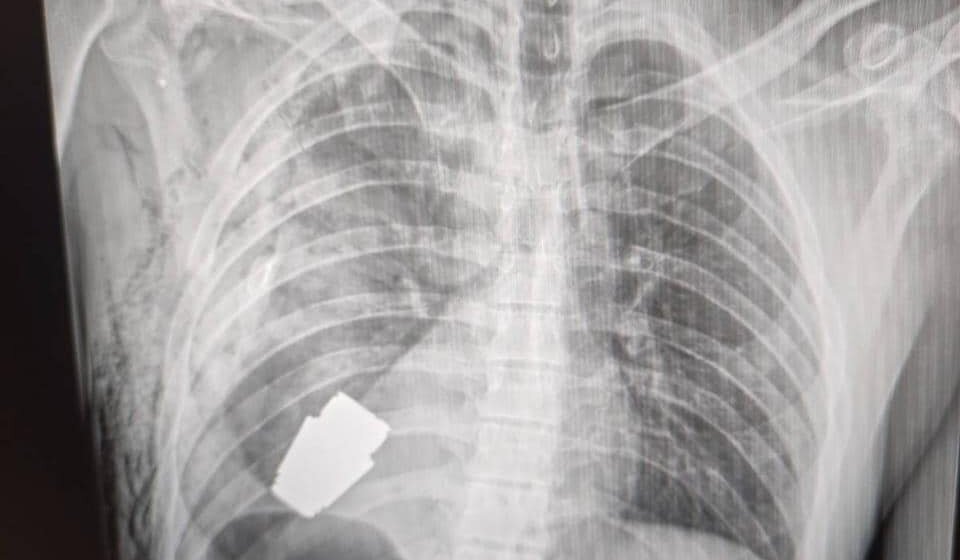

Hirurzi su uklonili eksplozivnu napravu tačno ispod srca povređenog vojnika, a dva vojnika su se pobrinula da operacija bude izvedena bezbedno, rekla je Hana Malijar, zamenica ministra odbrane Ukrajine. Ona je objavila i fotografiju na kojoj se vidi rendgenski snimak granate u telu vojnika.

„Vojni lekari su izvršili operaciju uklanjanja neeksplodirane VOG granate iz tela vojnika“, napisala je ona u objavi na Fejsbuku.

Operacija je izvedena bez upotrebe elektrokoagulacije – uobičajene metode za kontrolu krvarenja tokom operacije – jer je granata mogla da detonira u bilo kom trenutku, rekao je Maliar.

Geraščenko je rano u četvrtak na Telegramu napisao da je neeksplodirani deo granate izvađen ispod srca.

„Granata nije eksplodirala, ali je ostala eksplozivna“, rekao je on.